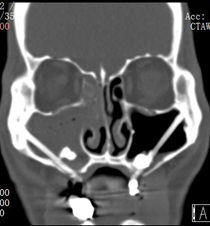

2、据统计牙源性鼻窦炎可能占所有慢性上颌窦炎的25%至40%,多半单侧发病,CT显示单侧上颌窦混浊的情况下牙源性鼻窦炎占比45%至75%。

CT显示单侧上颌窦混浊

1)鼻窦CT发现上颌窦浑浊,尤其单侧,需留意上列牙齿问题。常规的鼻窦CT现实不足的部分,需要进一步的专科检查以排除牙源问题。